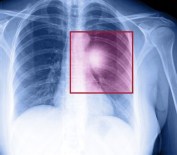

30 Kasım 2015 Pazartesi 16:40:20Doç. Dr. Kılıçkap Açıklaması 'Son 5 Yılda Akciğer Kanserine Yönelik Daha Etkili Tedaviler Geliştirildi'

Tıbbi Onkoloji Derneği Yönetim Kurulu Üyesi ve Hacettepe Üniversitesi Tıbbi Onkoloji Bilim Dalı Öğretim Üyesi Doç. Dr. Saadettin Kılıçkap, son 5 yılda akciğer kanserine yönelik daha etkili tedavilerin geliştirildiğini söyledi.